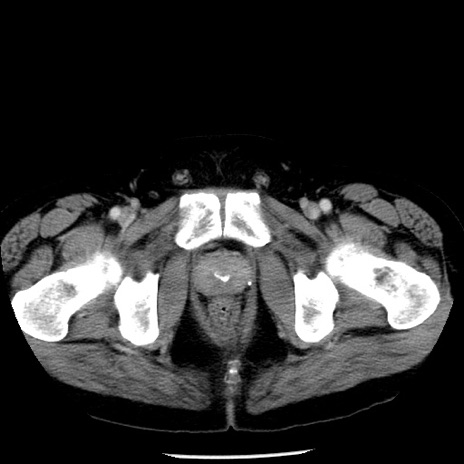

症例29(横断像)

【症例】40歳代男性

【現病歴】2日前から胃痛あり。徐々に周期的な激痛に変化した。本日になっても激痛があるため受診。

【身体所見】意識清明、BT 38-39℃台あり、腹部:膨満、やや硬、右下腹部に圧痛あり。

【データ】WBC 8500、CRP 23.26